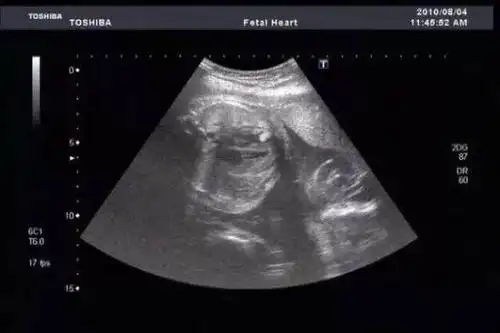

胡杏儿晒胎儿b超照 宝宝小脚丫超可爱(图)